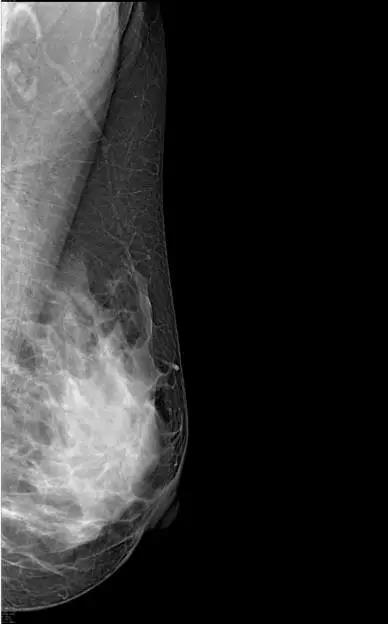

临床图像

R-CC

L-CC

R-MLO

L-MLO